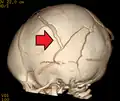

3D CT reconstruction showing a skull fracture in an infant 3D CT reconstruction showing a skull fracture in an infant